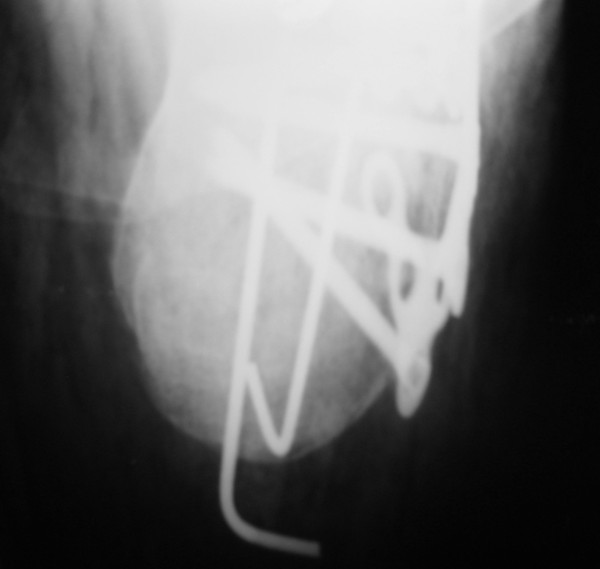

Операция проведена на 14е сутки после травмы. Фиксация блокируемой пластиной. Трудности - сложность репозиции; необходимость костной пластики (уложен измельченный трансплантат из гребня подвздошной кости 4,5х1,5х1см); множество мелких отломков; большой фрагмент наружной кортикальной пластинки, закрывающий картину в суставе.